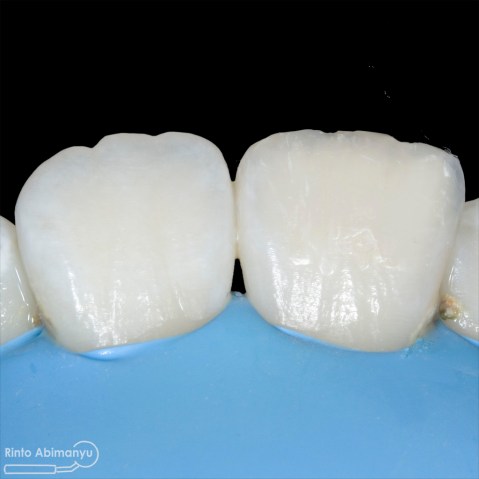

Setalah pengisian usahakan kamar pulpa dibersihkan dari sisa2 siler dan kotoran2 agar bahan adhesive yang kita pakai untuk restorasi dapat melekat maksimal.. Untuk basis saya menggunakan X-tra Base (Voco) kemudian diatasnya memakai komposit Z 350 XT (3M)…

Setelah itu dilakukan pengambilan ronsen kembali…

Alhamdulillah perawatan ini tidak ada kendala dan bisa diselesaikan dalam satu kali kunjungan langsung dua gigi… Ronsen sangat penting dalam prosedur perawatan saluran akar, jadi pesan saya adalah “No Xray, No Endo” 🙂